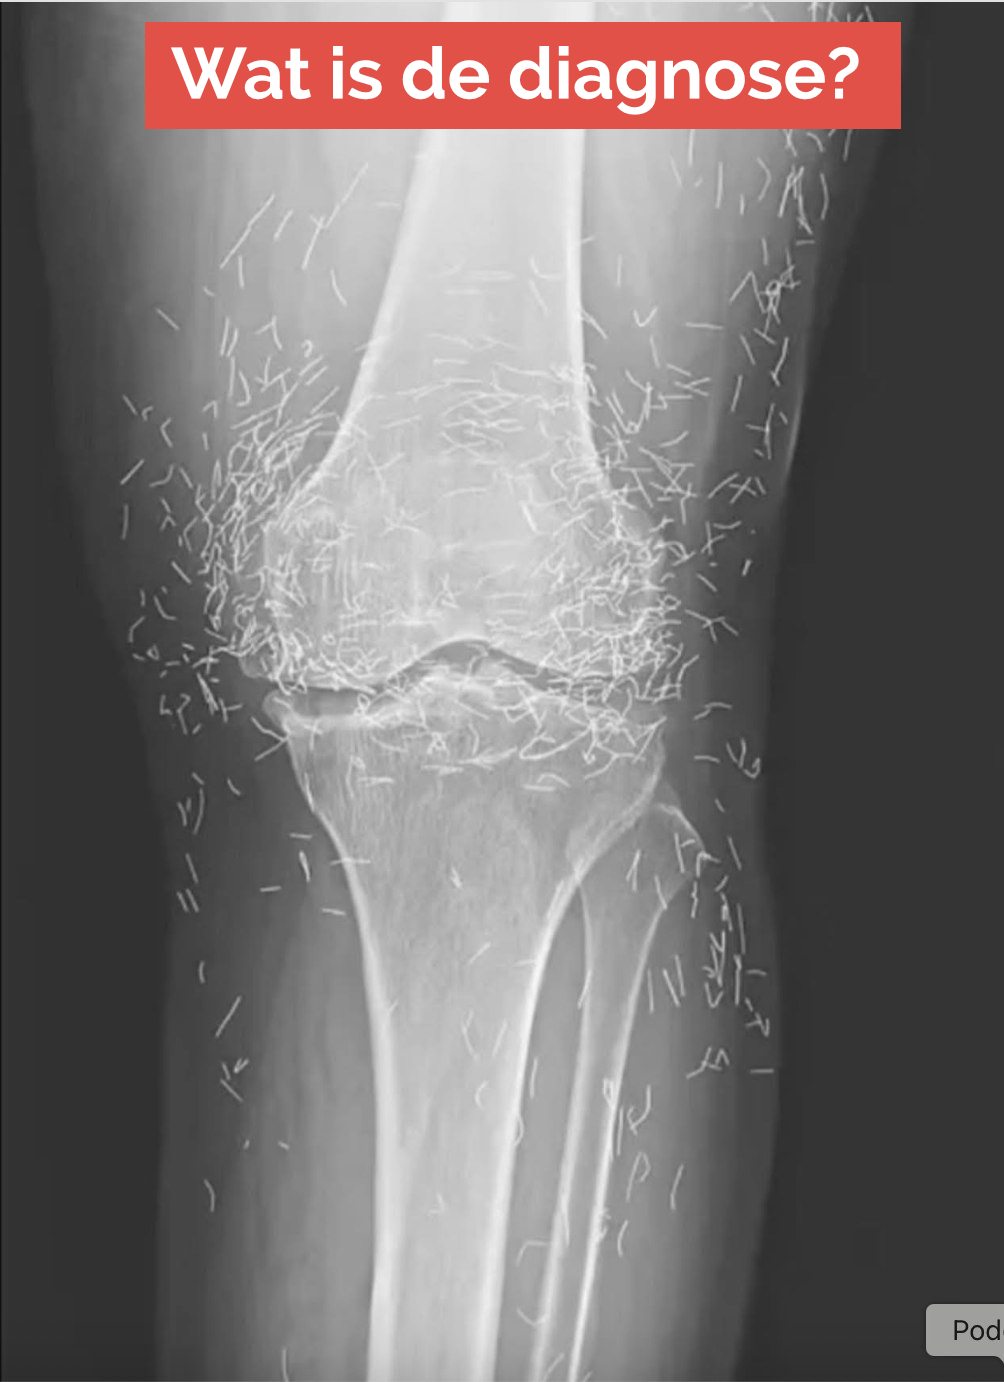

Artsen vinden ‘goudmijn’ in knieën van vrouw

Toen een 65-jarige Zuid-Koreaanse vrouw zich meldde met kniepijn, verwachtten de artsen niet dat ze goud zouden vinden. Maar dat was precies wat ze vonden.